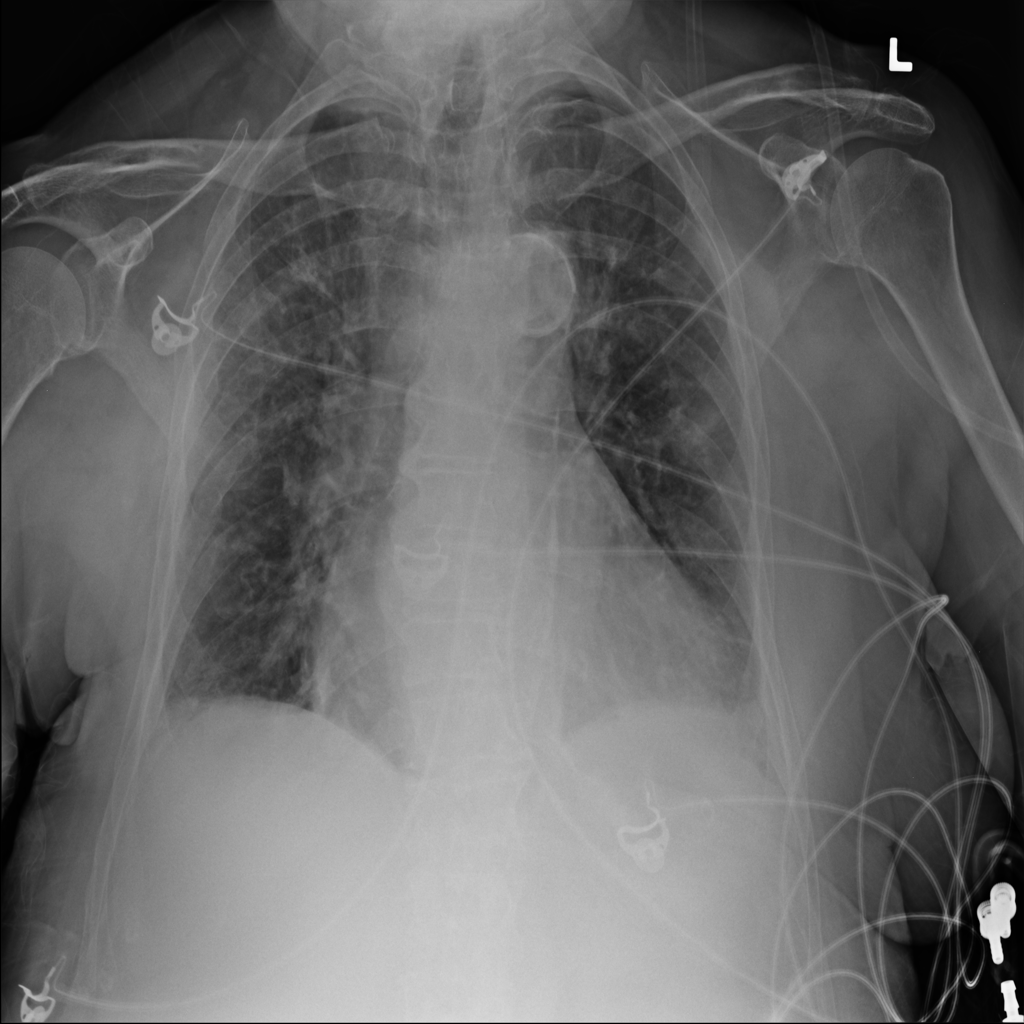

Pneumothorax

Pneumothorax means air is present outside the lung in the pleural space, which can allow part of the lung to collapse. It is an important imaging finding because the size and clinical impact can vary widely.

Showing up to 90 reference images for Pneumothorax.

PAT-4639 · IMG-011Pneumothorax

PAT-4639 · IMG-011

AP